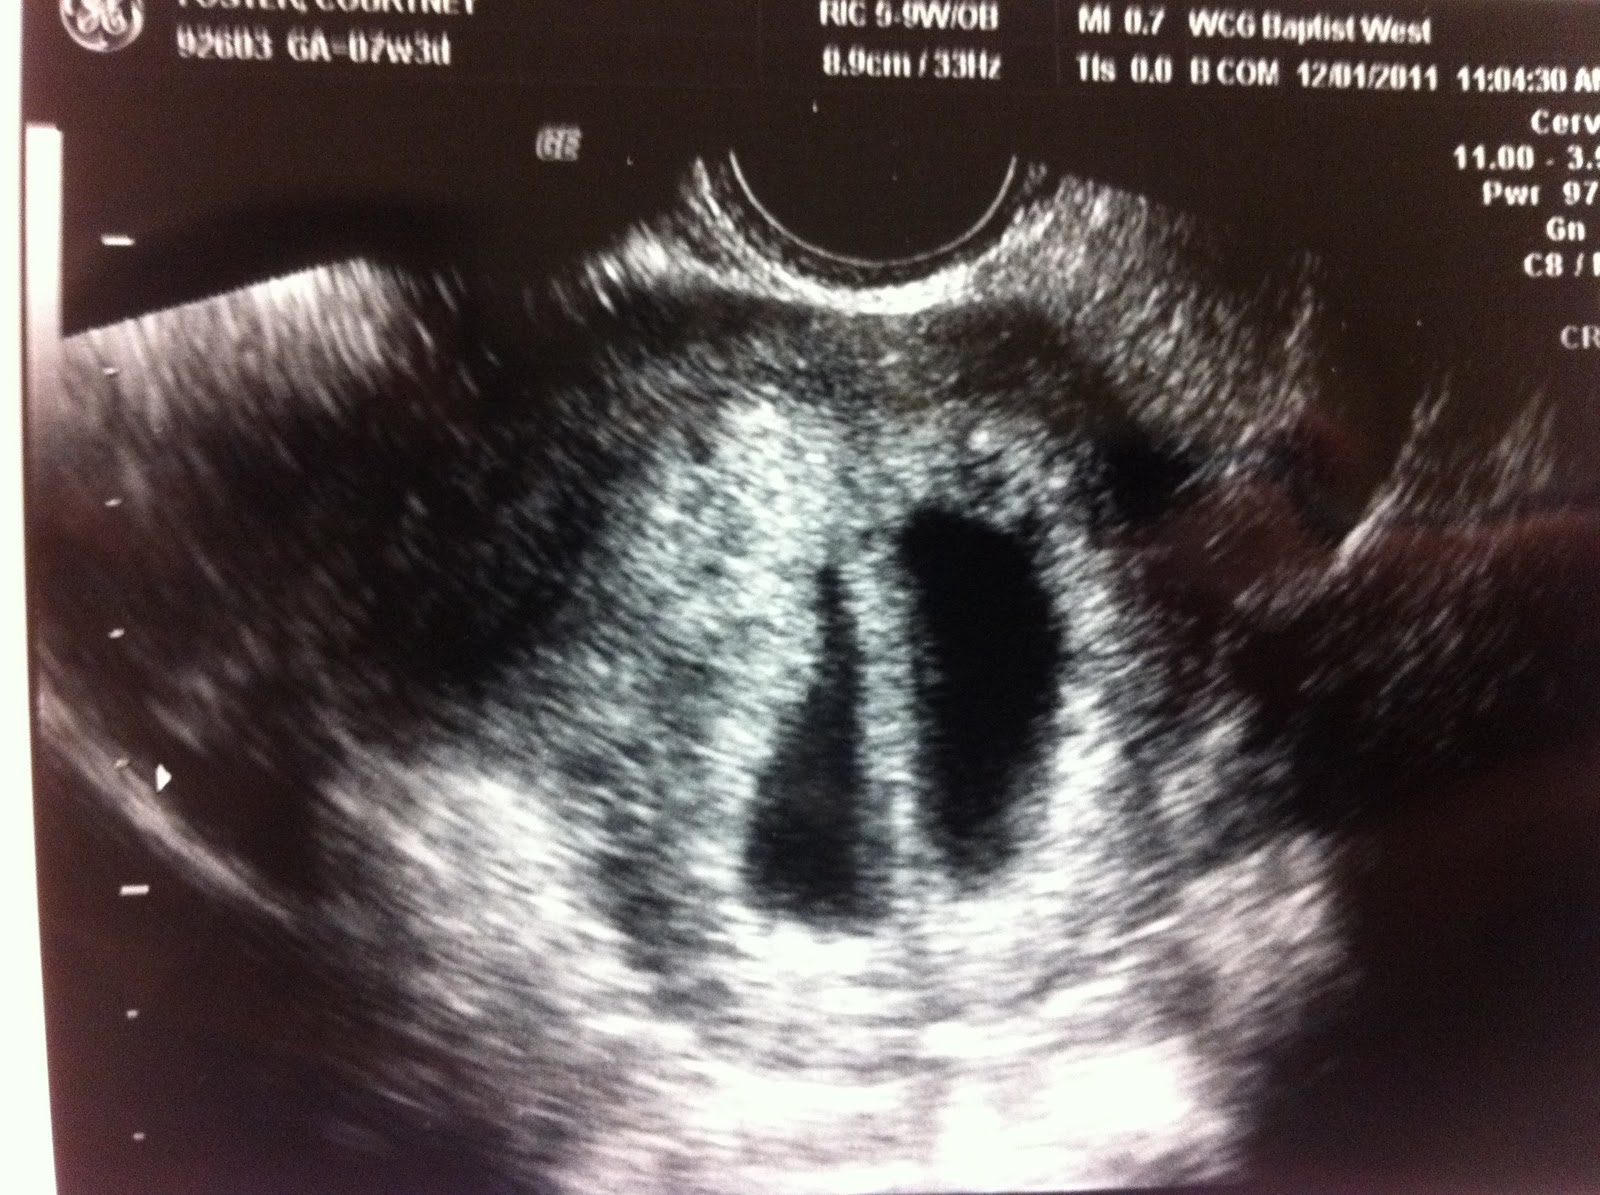

From foster-twins.blogspot.com

Twin Pregnancy Our first ultrasound How Early Can You Detect Twin Pregnancy On Ultrasound although the factors above may be signs of a twin pregnancy, the only sure way to know you’re pregnant with. During this time, the ultrasound technician will look for two gestational sacs in the uterus, which can indicate twins. at about 10 weeks an ultrasound can tell for sure if the babies are growing in their own amniotic. How Early Can You Detect Twin Pregnancy On Ultrasound.